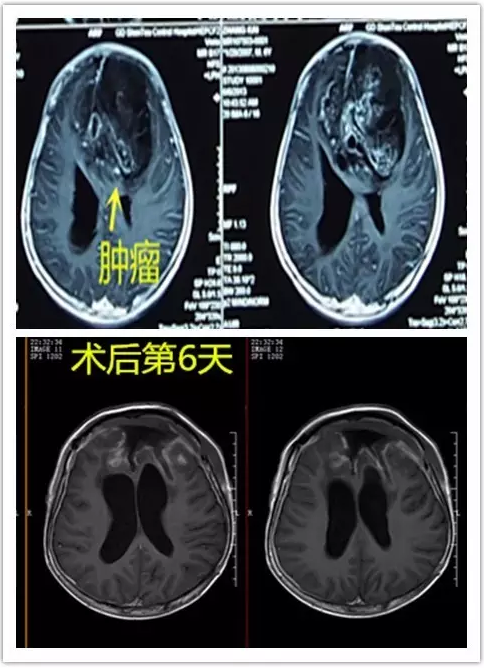

图3:术前术后磁共振对比,显示肿瘤全切

手术切除全部肿瘤是中枢神经细胞瘤的首选治疗方法,可辅助行放疗和化疗。大多数中枢神经细胞瘤的组织学及生物学行为为良性或低度恶性,预后良好,部分预后较差。细胞增殖指数的增加、核分裂象、局部坏死、血管内皮增生及 GFAP的阳性表达可能提示预后不良。大多数报道的中枢神经细胞瘤分化好,一般少有间变。虽然部分中枢神经细胞瘤有间变,但是对预后的影响仍然不确切。MIB-1指数可反映肿瘤的增殖活性,在一定程度上可预示复发和预后。有学者认为可将 MBI-l指数>2%作为中枢神经细胞瘤复发的标准, 当MIB-1>2%时提示有中枢神经细胞瘤侵袭性倾向,术后复发率高,预后不良。Ades等研究表明MBI-1指数在预示预后方面比间变的组织学特点更有价值,认为以3%为MIB-1的标记指数是一个界点,尤其对肿瘤全切或部分切除行辅助放疗后的患者预后价值更大。

综上所述,中枢神经细胞瘤的病理学诊断要点是特征性的无核神经原纤维基质岛结构、形态较为一致的圆形或卵圆形细胞、蜂窝状结构、芽枝样毛细血管,典型的影像学表现有助于鉴别诊断。 手术治疗是中枢神经细胞瘤首选治疗方法,可辅助行放疗和化疗。